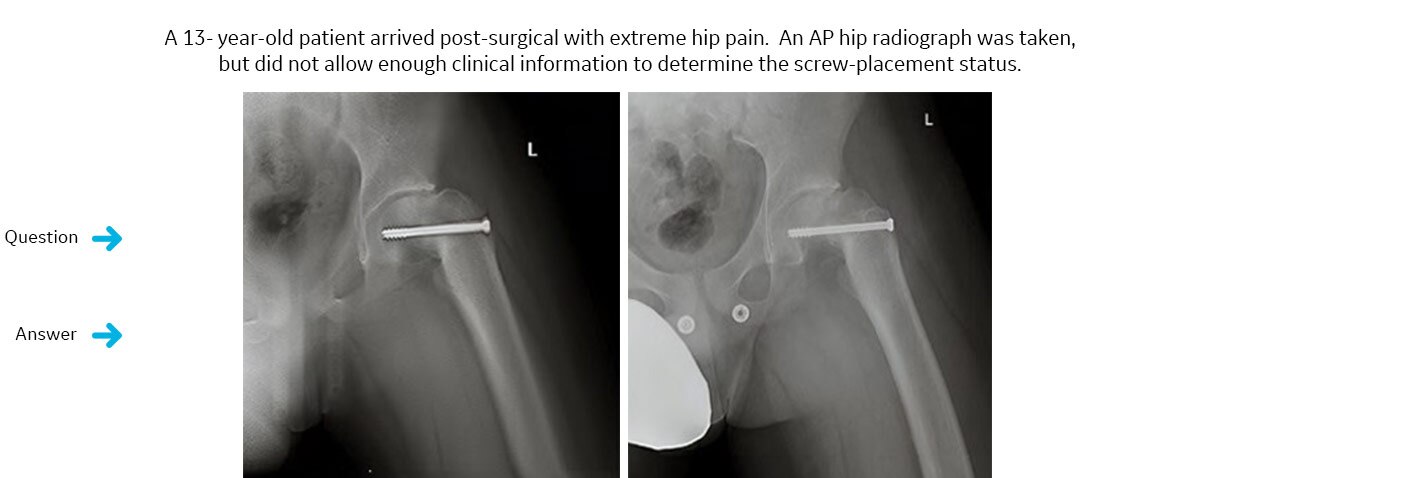

Had an implanted screw invaded the hip joint space?

VolumeRAD study ordered. VolumeRAD allowed removal of overlying structures, helping to enable a confident diagnosis.The definitive answer: no.

A single-slice interval from the VolumeRAD data revealed that the implanted screw had not invaded the joint space. The patient underwent secondary surgery and proper implant placement was confirmed.